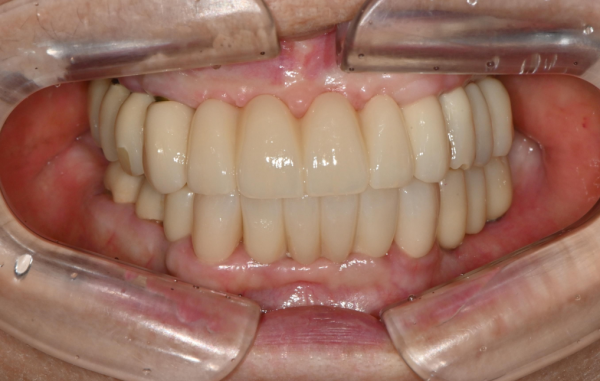

치료 후 변화

최종 보철 장착 후

✔ 틀니 탈락 없음

✔ 단단한 음식 섭취 가능

✔ 자연스러운 발음

✔ 저작력 회복

현재는 정기검진으로 내원하시며

가족들과 외식도 자주 하신다고 합니다.

최근 내원 시 이렇게 말씀하셨습니다.

“요즘 내가 제일 잘 먹는다네. 고기도 잘 씹혀요.”

7월 : 전악 고정성 보철 완성